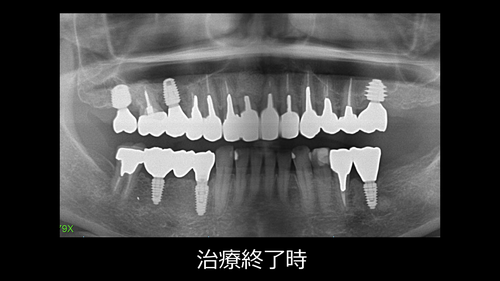

今日は上下に合計6本のインプラントを埋入し、古い金属も全て白くした症例をご紹介致します。

初診時から12か月後に、全ての治療が終わりました。

インプラント埋入は全てフリーハンドで行っていますが、素晴らしいポジションに入っています。(←自分で褒めてしまう)